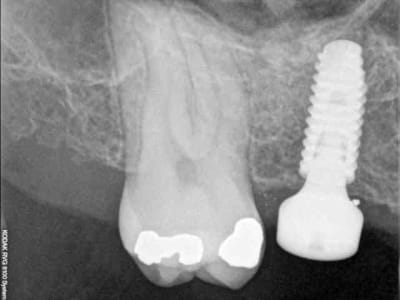

je sais pas si c'est un produit miracle, mais pour les sinus lift, c'est fantastique.

outre le fait de stabiliser un implant dans un sinus type SA4, pas de risque de voir partir le produit comme avec les granules de bioos et autres..

l'autre avantage est de ne pas avoir à mettre de membrane de recouvrement.

je suis donc hyper satisfait du résultat.

jugez plutôt...

quasiment 6 mois entre les deux interventions (sinus lift et mise à jour)

c'est surtout la qualité des trabéculations osseuses qui m'interpelle.

d'habitude, on voit toujours un peu de particules, ici, c'est vraiment top.